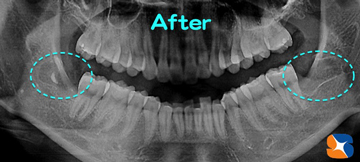

横向きの親知らずを左右ダブル抜歯

コラム「横向きの親知らずを左右ダブル抜歯」の画像